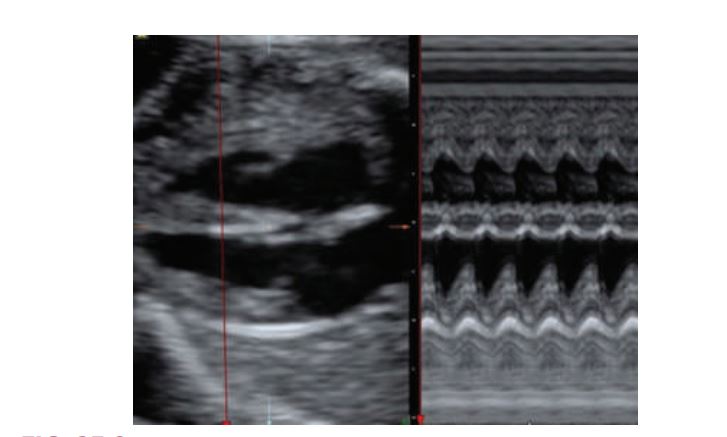

Two-dimensional and M-mode of the ventricular cavities. On the motion mode, time is depicted along the horizontal axis (dots along the top of the image). The distance between two dots represents 1second. Distance is located along the vertical axis. The aorta is shown as the two parallel lines moving as a “unit” through systole (pumping) and diastole (resting).

M-mode measurement of the fetal heart.IVS =

Intraventricular septum

Four-Chamber View: M-Mode